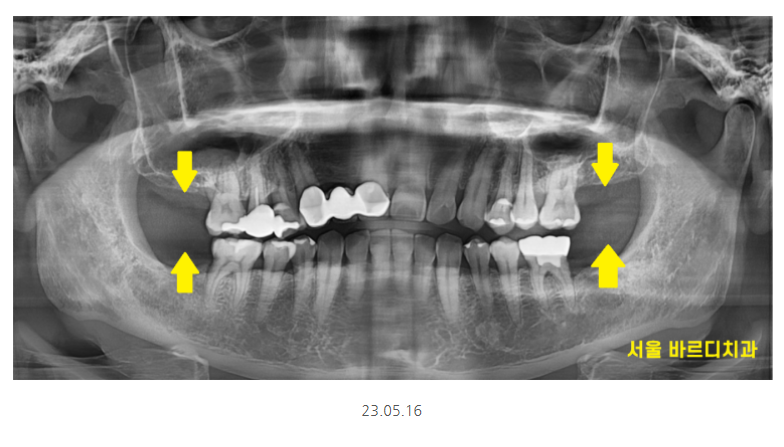

명일동 치과에서 수술 후 한 달 뒤

뼈 이식한 부분이 잘 만들어지고 있습니다.